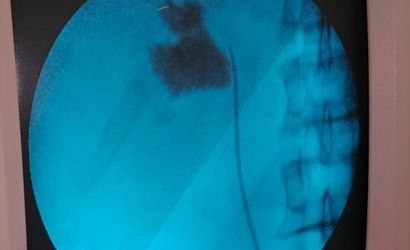

Kırşehir'de, Eğitim ve Araştırma Hastanesi'nde bir hastanın böbreğindeki 6 santimetrelik taş, kapalı ameliyat yöntemiyle alındı.

Hastaneye başvuran İlhami Çakır'ın yapılan kontrollerinde, sol böbreğinde 6 cm boyutunda bir taş tespit edildi. Üroloji Kliniği'nden Uzm. Dr. Talip Göktaş ve ekibi, kapalı böbrek taşı yöntemi PNL ile başarılı bir ameliyat gerçekleştirdi.

Ameliyat sonrası bir gün içinde taburcu olan Çakır, operasyon ekibine teşekkür etti. Uzm. Dr. Göktaş, hastaların bu yöntemle açık ameliyatlara göre daha hızlı bir iyileşme süreci yaşadığını belirterek, "Hastamız 1 gün sonra taburcu edildi. Bu yöntemle hastalarımız daha konforlu bir şekilde süreç atlatabiliyor. Son 5 yıl içinde hastanemizde 50'nin üzerinde bu tarz başarılı ameliyat gerçekleştirdik," ifadesini kullandı.